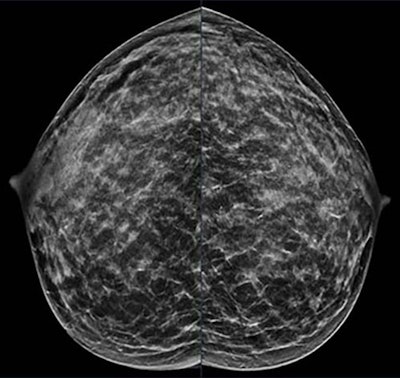

A 40-year-old patient presents for routine screening with a family history of the paternal grandmother, age 55. Extremely dense breast tissue is noted on mammography right and left craniocaudal view.RSNA